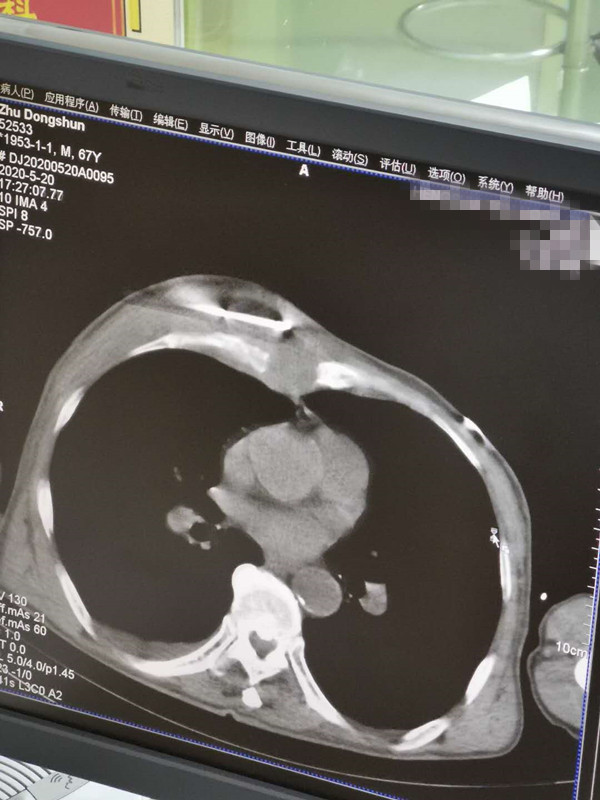

67岁胸部肉瘤氩氦刀冷冻消融

发布人:美国氩氦刀技术官方网站    发布时间:2020/5/21 14:53:37